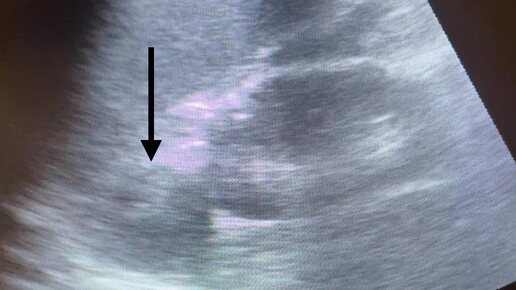

При подозрении на аденому надпочечника всегда рекомендую КТ, либо МРТ, объясняя это тем, что маленькие размеры аденомы (до 1 см) могут быть

При подозрении на аденому надпочечника всегда рекомендую КТ, либо МРТ, объясняя это тем, что маленькие размеры аденомы (до 1 см) могут быть не видны на узи, и предположительный диагноз о её наличии моё исследование полностью не снимет. Да и в целом принадлежность образования надпочечника именно к аденоме можно с высокой долей вероятности предположить по характеру интенсивного накопления и быстрого «вымывания» контрастного препарата, что опять же отсылает нас к КТ/МРТ...